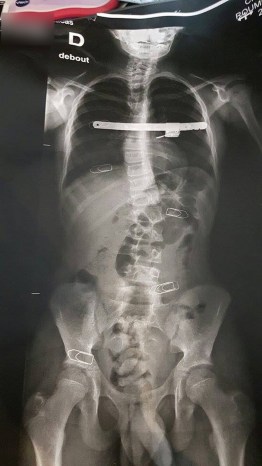

Le port d’un corset a donc été prescrit.

Il doit le mettre la nuit surtout mais aussi le plus possible en journée.

Par contre : Le 1er soir avec le corset, impossible d’attraper ses couvertures et de se tourner. Toute une technique à apprendre. Et c’en est fini du camping à dormir sur un lit de camp, il a aussi fallu changer ça. Prévoir des tricots de corps spéciaux, sans coutures à porter sous le corset à même le corps. Visite tous les 3 mois pour ajuster le corset. Et il faut le changer au bout d’un moment bien sur.

Bonne nouvelle, au bout de 3 ans plus de corset, sinon il aurait fallu opérer, mais un suivi tout de même. Il a été très courageux ce gamin.